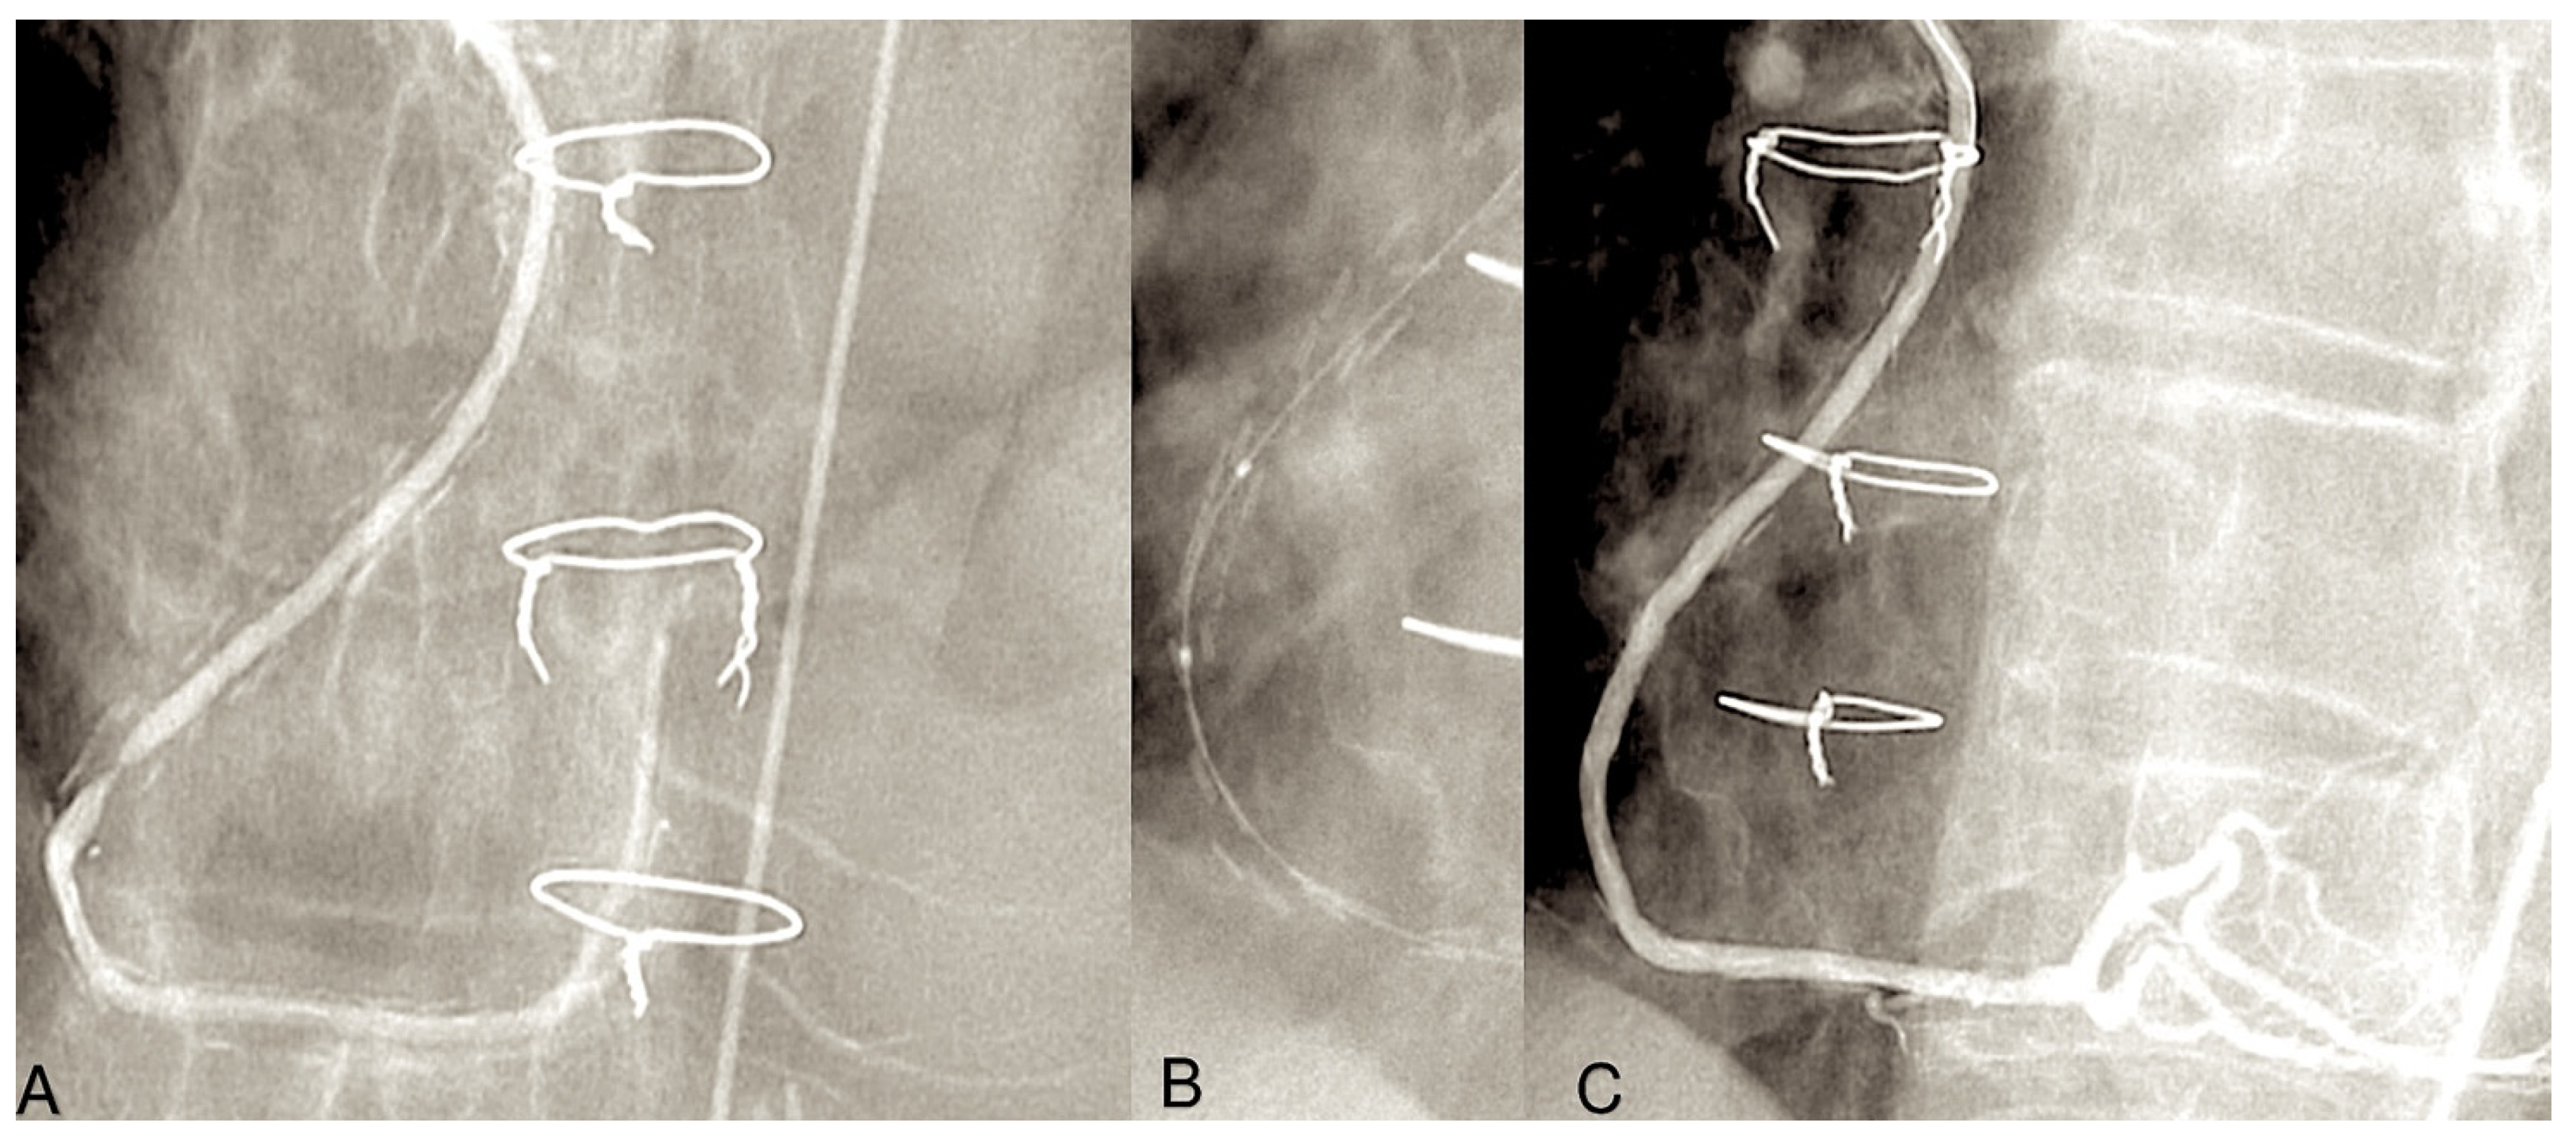

As a general principle, the surgeon advocates proximal anastomosis to the anterior portion of ascending aorta. Proximal anastomoses for individual conduits are achieved through the use of a suture to affix the graft end to side to an aortotomy in the proximal ascending aorta. A circular aperture measuring 3 mm in diameter is created in the aortic wall using a punch. The graft is then secured directly to the aorta using 7/0 Prolene sutures (Figure 1A,B).

Figure 1.

The illustration depicts a coronary artery bypass graft (CABG) procedure utilising radial artery (RA), saphenous vein grafts (SVGs), and left internal thoracic artery (LITA) (A,B). (A): The SVGs have been anastomosed to the posterior descending artery branch of the right coronary artery (1) and to the obtuse branch of the left coronary circumflex artery. The proximal anastomosis is secured on the ascending aorta (yellow arrow). The LITA has been anastomosed to the left anterior descending artery (LAD). (B): The RA (2) is anastomosed distally on the right coronary artery and proximally on the ascending aorta (yellow arrow), while the LITA is anastomosed on the LAD. Note that the venous graft size is greater than the arterial graft size.

However, in cases of target vessels situated in the proximal obtuse marginal position, the graft utilised for CABG is anastomosed anteriorly or alternatively on the opposite side of the aorta through the transverse sinus (Figure 2A,B).

Figure 2.

The figure illustrates the post-processing of CT angiography of CABG using volume rendering (A) and two-dimensional curved imaging with automatic tracking. (B): CT angiographic control of the radial artery at 27 years. The radial artery (yellow arrow) was utilised as the second target conduit on the second obtuse branch of the left coronary circumflex artery and the posterior descending artery. Abbreviations: CABG, coronary artery bypass grafting; CT, computed tomography.